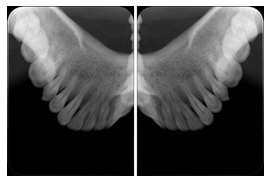

3. A dental provider wishes to capture a series of DICOM IO images for the patient’s dentition. The tooth morphology, teeth are divided into molars, premolars, canines and incisors, and a number of images for each jaw. The anatomic information was captured utilizing the triplet of schema. This standard code sequence is based on ISO 3950-2010, Dentistry - Designation system for teeth and areas of the oral cavity.

Every IO image should have anatomic information either through the primary or modifier sequence.

In most standard cases, images are oriented in structured layouts. These structured displays are useful to be shared between providers for reference purposes.

Table OO.1.1-1 shows structured display standard templates, where Viewset ID is based on the Japanese Society for Oral and Maxillofacial Radiology (JSOMR) classification provided by JIRA (Japan Medical Imaging and Radiological Systems Industries Association, www.jira-net.or.jp). Expected or typical teeth to be imaged location, region and designation codes are based on ISO 3950-2010, Dentistry - Designation system for teeth and areas of the oral cavity. For all the hanging protocols listed in OO.1.1-1, the value to use for Hanging Protocol Creator (0072,0008) is "JSOMR" and the value to use for Hanging Protocol Name (0072,0002) does not include "JSOMR" (e.g., "DL-S001A", not "JSOMR DL-S001A").